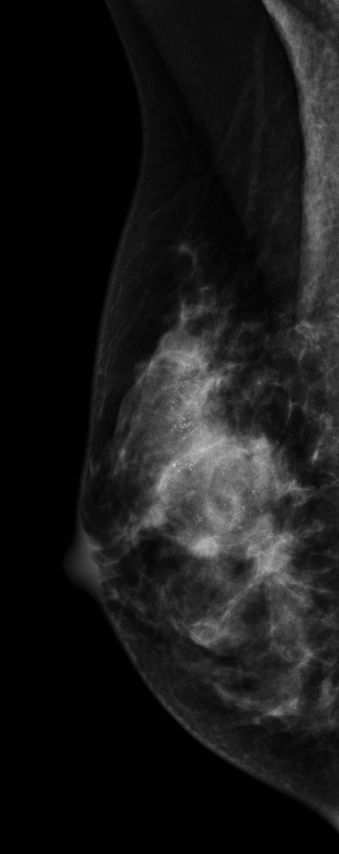

Vôi hóa nghi ngờ ác tính ở vú (Suspicious breast calcifications)